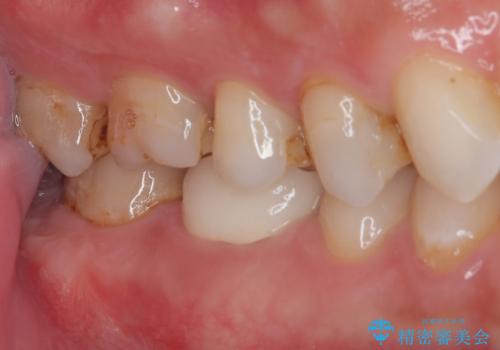

治療後特に問題もなく見た目、噛み合わせともに満足していただけました。

特に舌感が良いと喜んでくれました。

色については今後ホワイトニングをするので明るめをご希望されました。

オールセラミッククラウンは精密な型どりを行っているため、虫歯の再発リスクも少ないです。

嚙む力が強いのでマウスピースをこれから使用してもらう予定です。